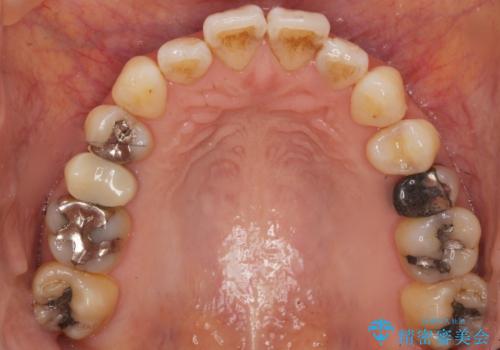

- 歯が欠けてしまったことを主訴に来院された患者様です。

欠けている奥歯(左上5)は失活歯で、保険内の銀の詰め物(メタルアンレー)で治療されていました。

金属の詰め物と土台を除去し、ファイバーコア(金属を使わない強くてしなやかな土台)を植立したのちセラミッククラウンによる補綴治療を行いました。

精査したところ、右上の奥歯(右上5)に根尖病変を認めたため、こちらは根管治療後にセラミッククラウンによる補綴を行いました。